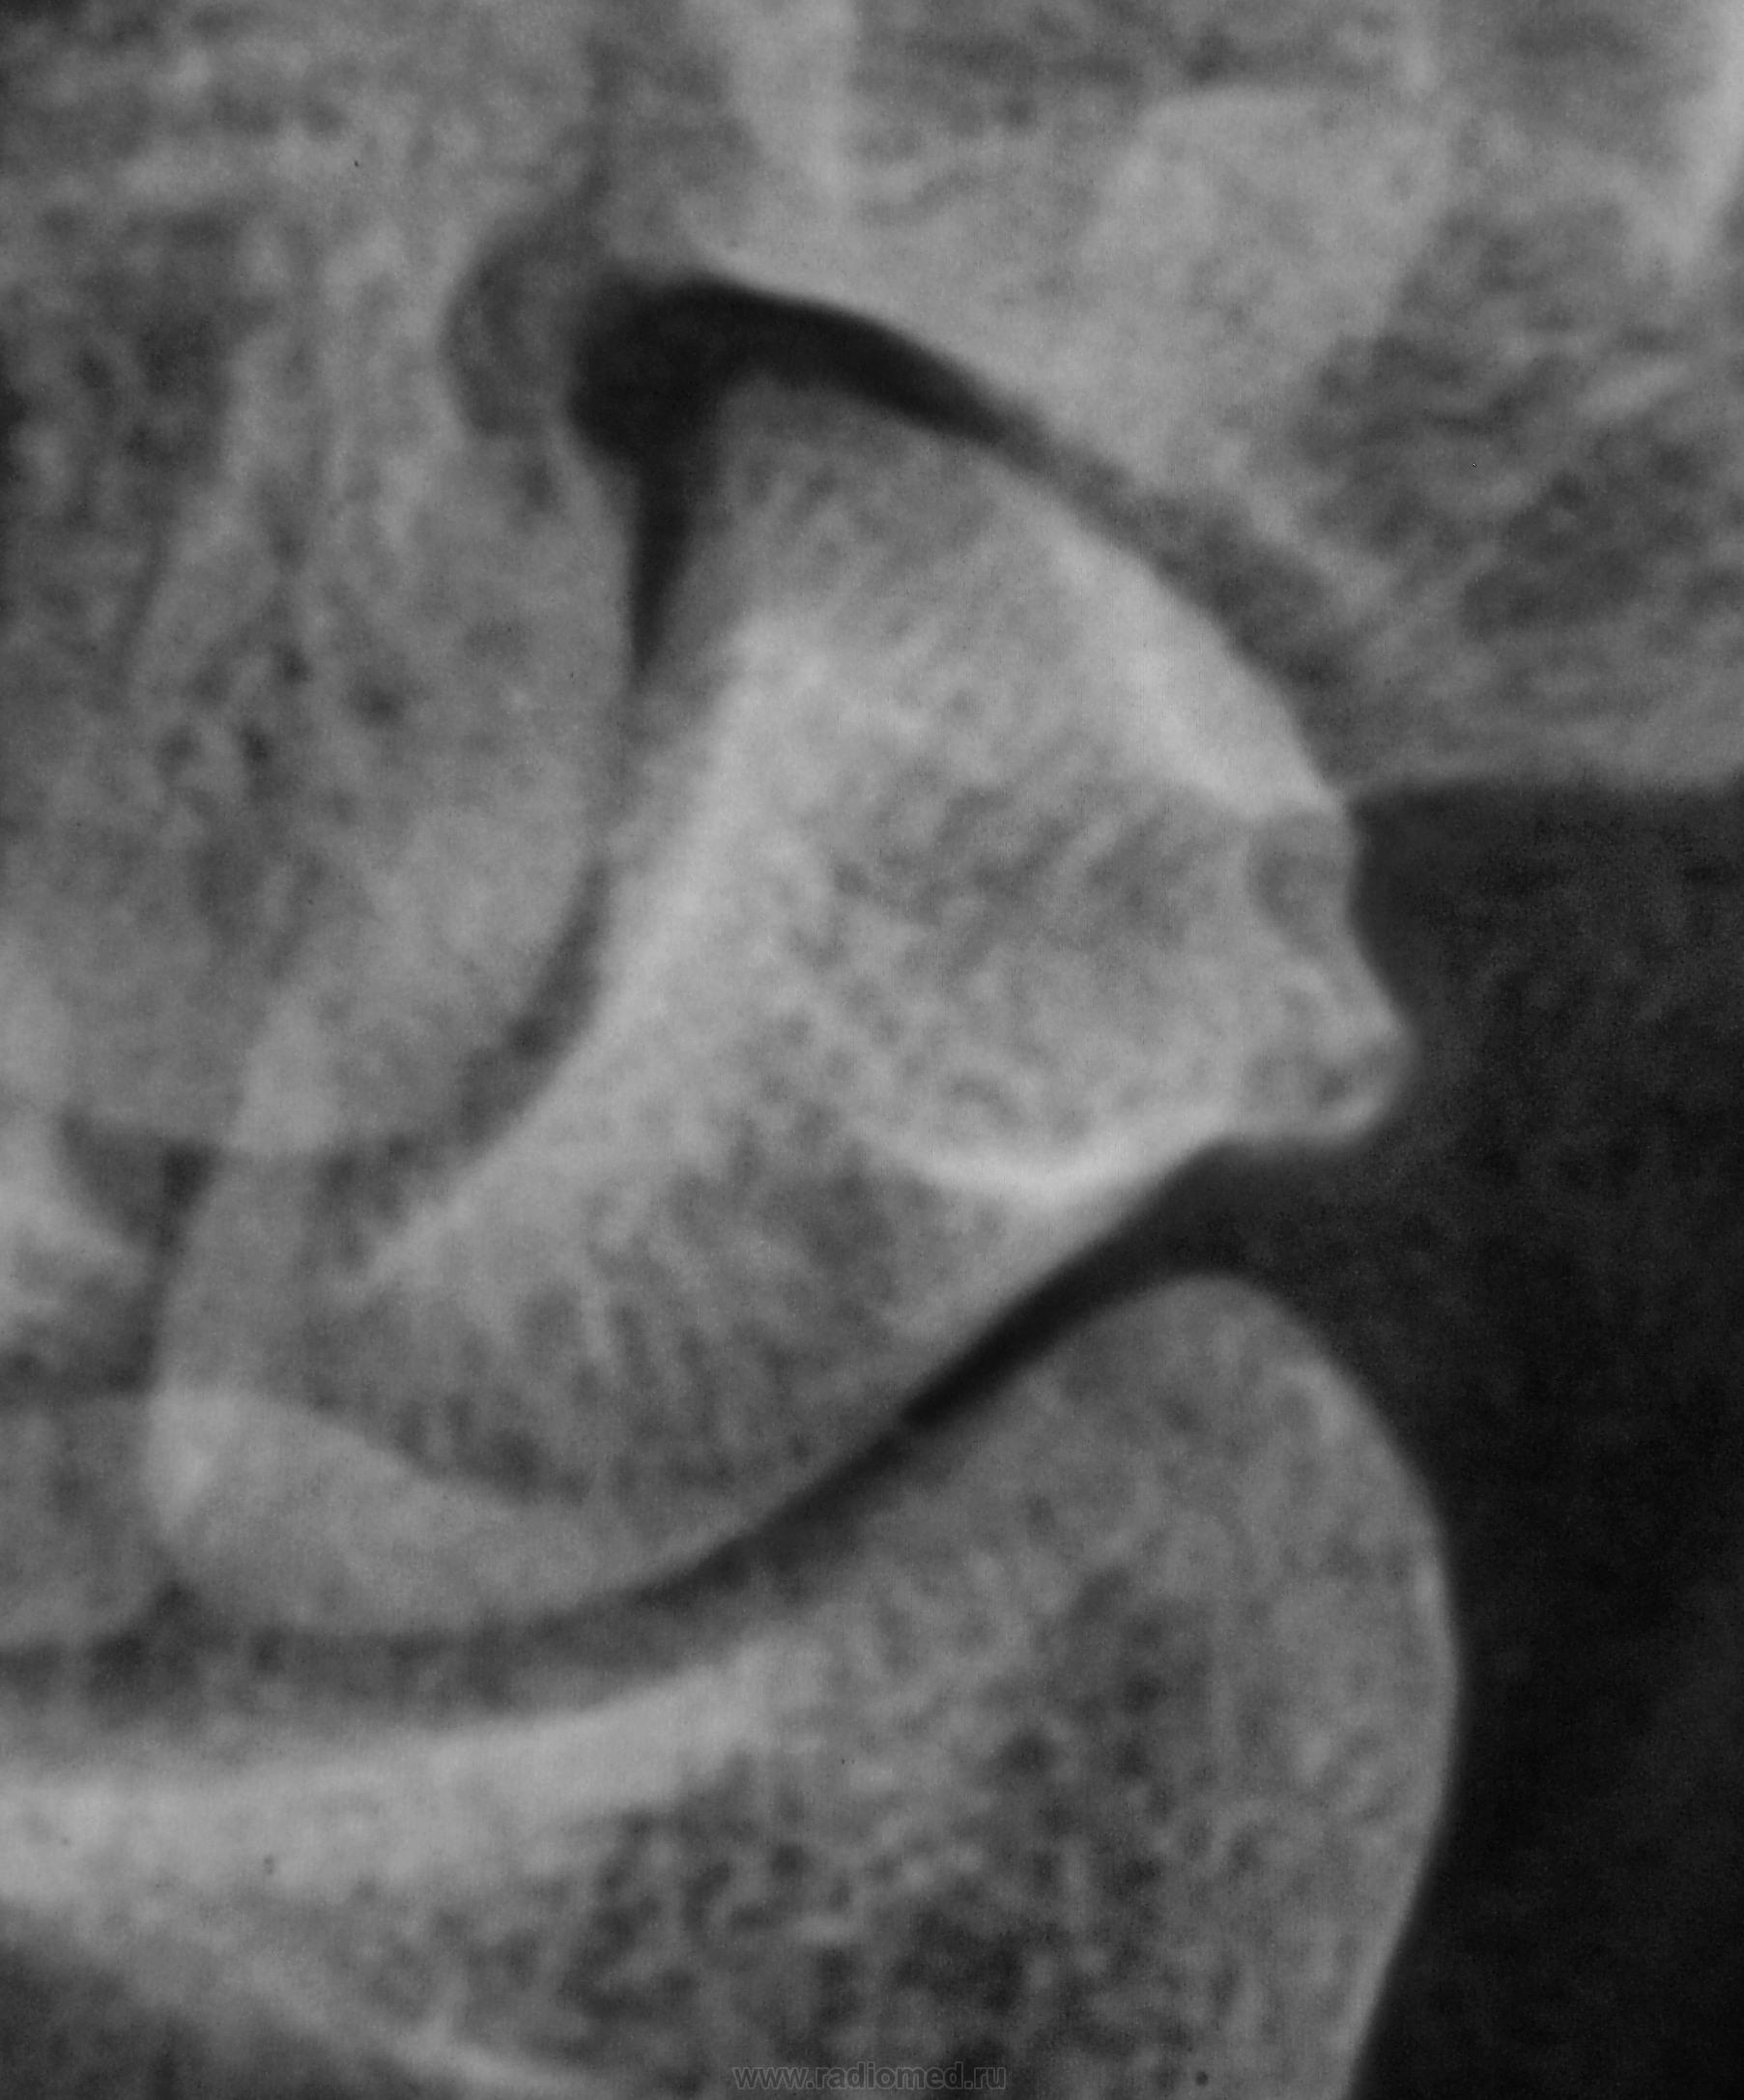

Пациент направлен хирургом на рентгенографию лучезапястного сустава с подозрением на артроз.

Какие мнения будут уважаемые коллеги?

tuberculum ossis scaphoidei